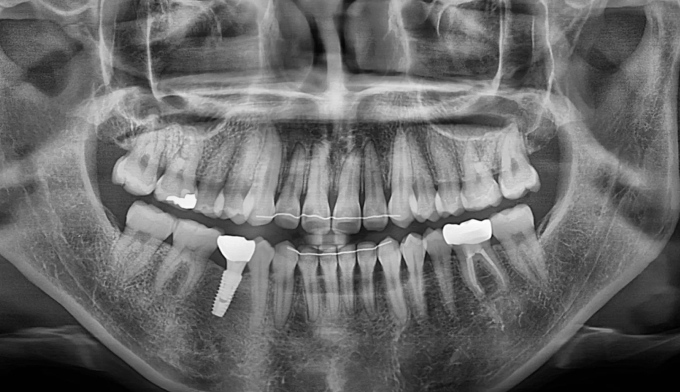

돌출입과 불규칙한 앞니를 가지고 있습니다. 그리고 아래쪽에 ‘임플란트’가 있습니다.

임플란트는 뼈와 강력히 결합되어 있기 때문에 교정치료로 절대 움직일 수 없습니다. 따라서 해당 부위는 절대 교정치료로 움직일 수 없다는 제한점이 있는 상태에서 교정치료를 진행하게 되었습니다.

돌출입을 해소하고 앞니를 가지런하게 만들기 위한 공간을 만드는 과정중에는 저 임플란트를 꼭 제거해야 했으나, 최대한 발치 없이 교정을 진행하였습니다.

후방이동이 불가하므로 악궁확장을 통하여 공간확보를 시도하였고, 동시에 돌출감도 해소되었습니다.

최종적으로 임플란트의 존재때문에 중심선을 맞추지는 못했으나 환자분은 너무 만족해하셨습니다.

총 치료기간은 14개월 소요되었습니다.